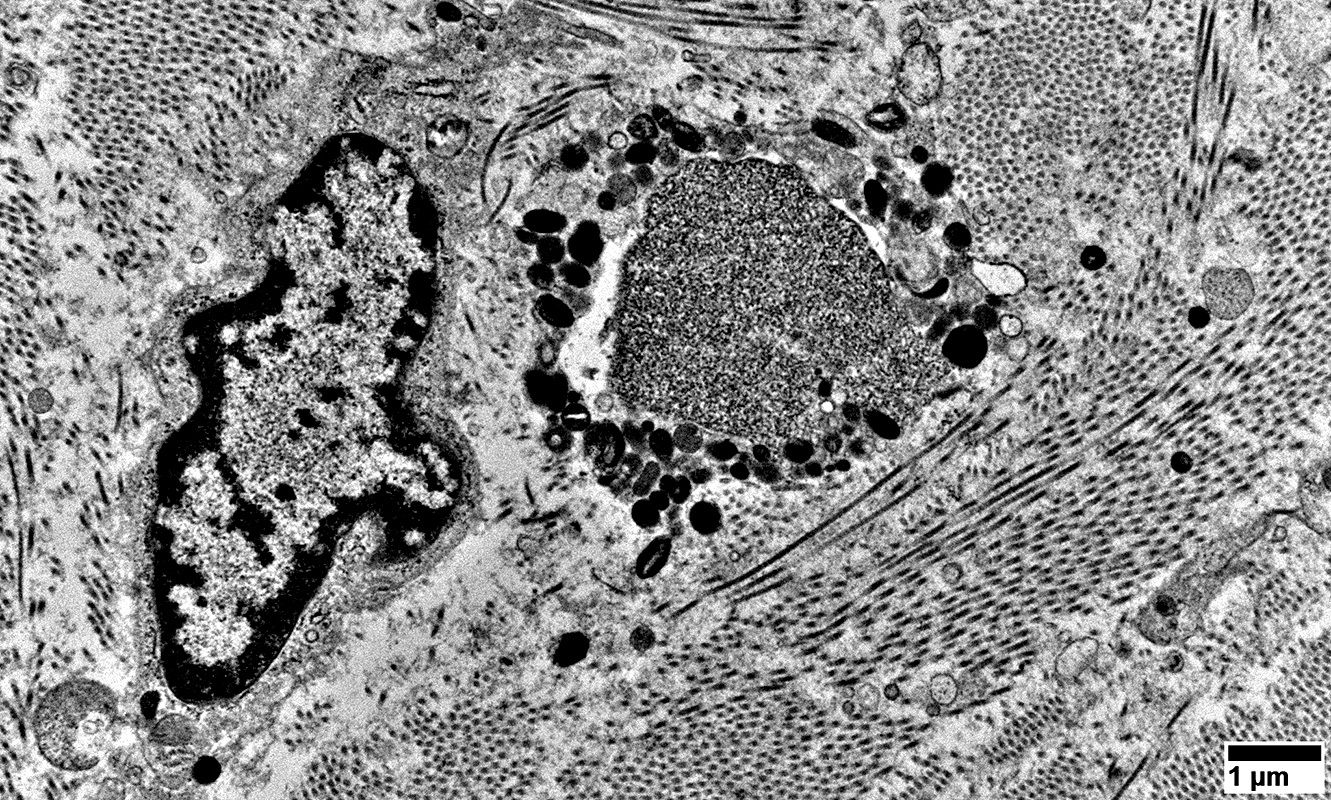

Regenerating Axons

Cluster of processes

Tubulovesicular profiles surrounded by Organelles, including many mitochondria

No surrounding Schwann cell cytoplasm

From: R Schmidt

Mixed contents: Tubulovesicular profiles & Organelles